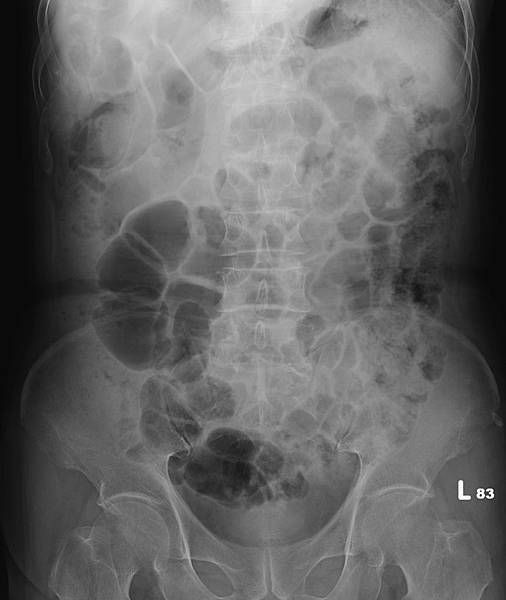

類似的病例很多,下面是上週門診時的胃酸逆流病例,KUB如下:

72歲女性,乙狀結腸(黃箭頭)充滿糞便,但她會告訴你,她每天都有解便。如上圖所示,這樣的病例,病人直腸(藍箭頭)糞便清得很乾淨。